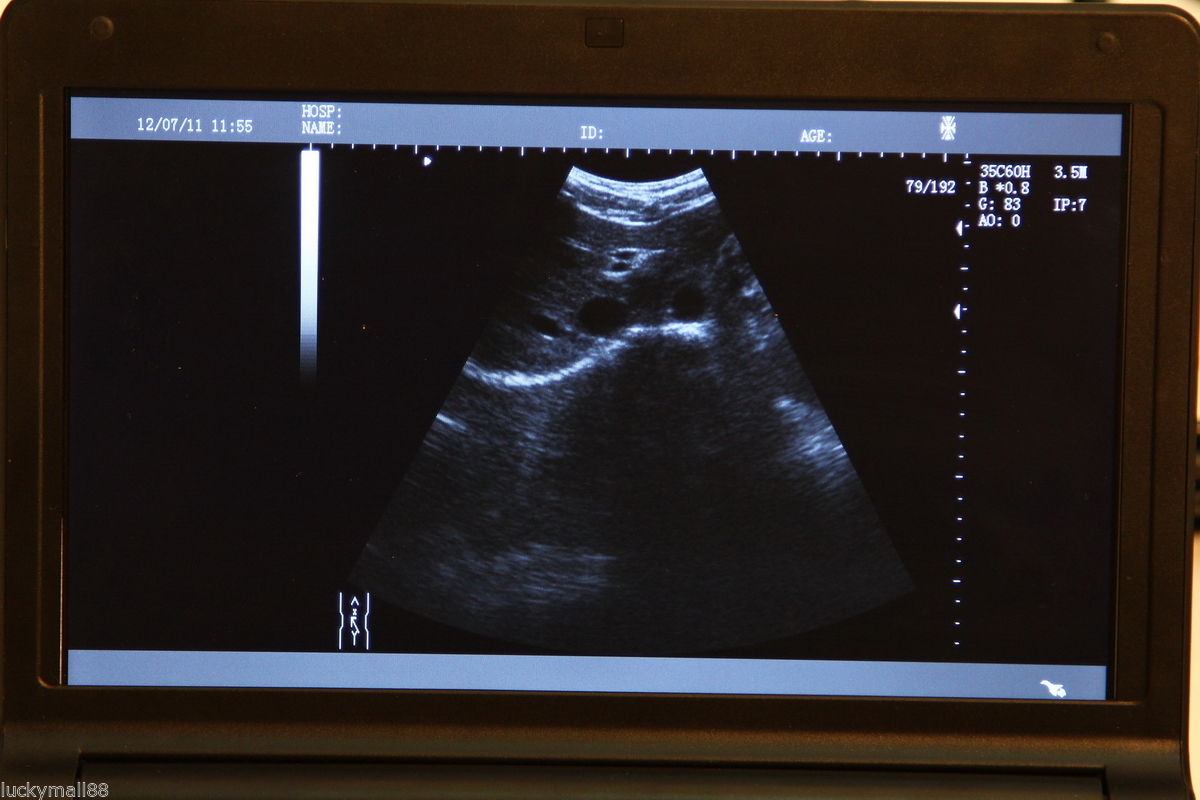

Ultrasound Scanner Laptop Machine Ultrasonic Machine Convex Rectal Transducer